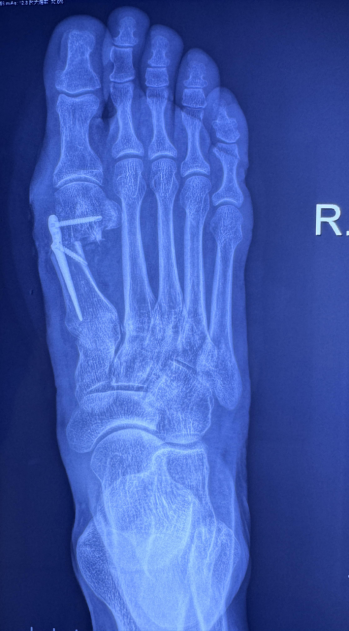

该患者完善术前各项准备后,于收住院第二日在全麻下行 右足拇翻截骨矫形内固定术,手术顺利,病情稳定,预后良好。

术后 影像学示:外翻角矫正至正常范围,跖骨间角恢复至正常范围。

本次我院接诊的这位患者足拇外翻多年,且在近六个月前出现足部疼痛并进行性加重,日常生活都受到了极大的限制。在我院骨科主任周昊嵬的带领下,医疗团队对该患者的病例进行了案例讨论及术前病例分析并制定了详细的手术计划,最终决定为该患者采用第三代微创拇外翻技术为其进行治疗。在麻醉科与手术室相关工作人员的紧密配合下,手术顺利完成。术后患者患足外观恢复良好。